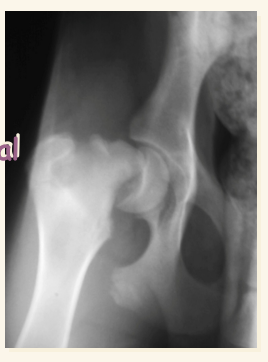

Necrosis avascular CF o Enfermedad de Legg-Calve-Perthes LO SUELE PREGUNTAR

- En cachorros de razas pequeñas

- Por defecto de vascularizacion de la cabeza y cuello femorales, cojera sobre todo en frio.

- Areas de radiolucidez en cabeza de fémur

- Deformación cabeza y cuello, se pierde siluheta de la cabeza del femur

- Muy dolorosa generalmente y con atrofia muscular

- Exéresis de CCF (cabeza y cuello femoral)